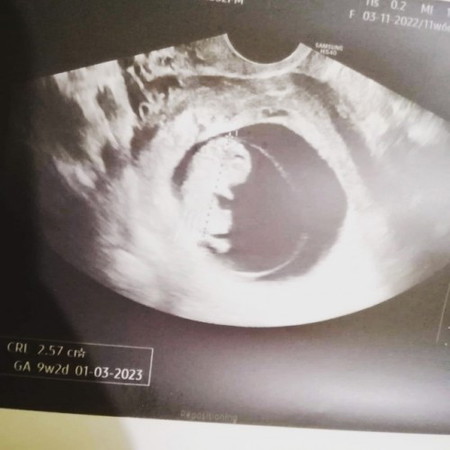

Hello..9 weeks na ako turning 10 weeks na sa tuesday.. Ever since na preggy ako my BROWN DISCHARGE ako and na diagnose na may sub.hemmorage sa loob. Start palang ng 3 weeks naka duphaston na ako at consistent bed rest. Lumiliit naman si hemorrage pero andon pa din sya 😔 wala na din akong brown discharge or spotting at wala namang sumasakit sa akin. OKAY na OKAY naman si baby sa loob,malusog na malusog naman sya. Complete vitamins pa din ako at meds. walang palya kahit sa check ups 🙂 Gusto ko lang magtanong sa mga kagaya ko na nakapanganak na? Possible bang hindi ito mawala pero okay si baby? Okay naman ang bloodtest ko although PCOS tlga ako both ovaries. Sana may makapansin at makasagot, naguguluhan na din kase ako e. #1stimemom #advicepls #pregnancy #firstbaby #pleasehelp #pregnancy

hello, finally nagdecide na kame magpalit ng OB ng husband ko. 3rd transv ko kanina dahil yung 1st at 2nd transv ko okay ang result pero dahil bagong OB na at gusto ko ng malaman bakit occasional ang brown discharge ko, nalaman na may hemmorage pala ako na hindi nakita sa mga prev. Transv ko 😔 I am now at 2 weeks full bedrest at still 3x duphaston. I hope maging okay ang lahat. Halos 3 weeks na akong nka duphaston nabawasan naman ang brown discharge at sana tuluyan ng mawala. 😔 Payo ko lang sa mga kagaya ko, if in doubt wag nag magpatumpik tumpik na kumuha ng new or second opinion sa ibang doctor kung hindi kayo satisfied sa recent doctor nyo. Hindi lang health nyo ang nakataya dito may little human na tayong dinadala. ♥️♥️♥️#1stimemom